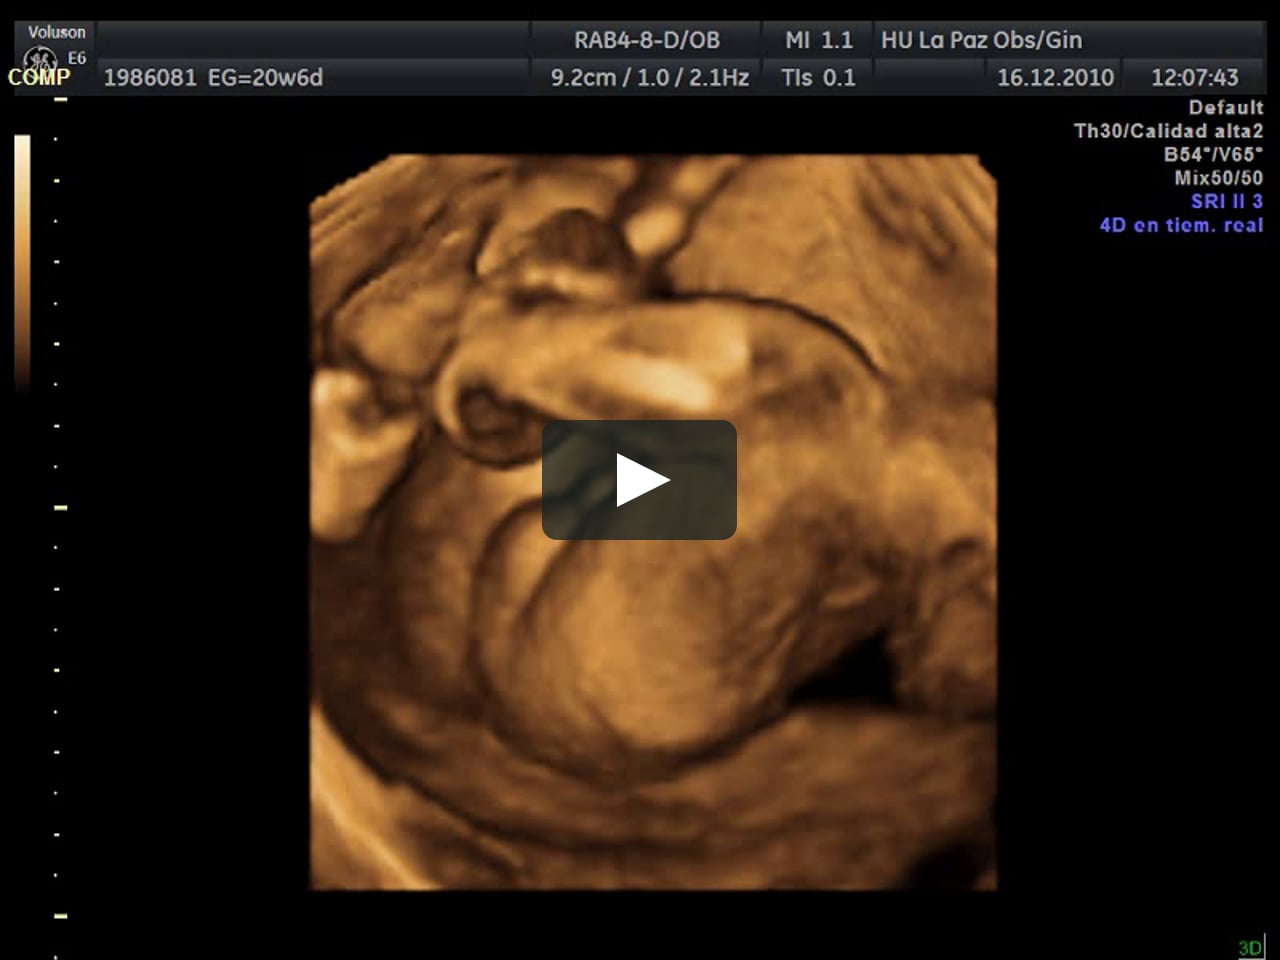

La eco 4-d se puede realizar en cualquier momento de la gestación mas se recomienda en 20 Semanas de embarazo o en la 21 semanas de embarazo no alén de la 30 por las proporciones de líquido amniótico y el tamaño del bebé. Aconsejamos que la cita se solicite entre la semana 26 y 30 de la gestación. El abdomen te crecerá más semana a semanaEstás en la semana 30 del embarazo y es ahora cuando notarás que la cadera y la pelvis se están aflojando y expandiendo para darle lugar al bebé que sigue creciendo.

Es que estoy de 30 semanas y cuando tenía como 21 me hize una 3D pero ahora quiero hacerme la 4 y no estoy segura cual es la diferencia. Durante la ecografía 4D - 5D de la semana 30 de embarazo las medidas de tu bebé son de 30 cm y su peso está alrededor de 1500 gramos. Cada vez que veo el video me emociono. Hola pancitas ustedes se han hecho ecografia 4D. Em resumo da ecografia que foi a 34D porque o relatório só vem no dia 30. Hicimos la ecografía 4D y todo fue perfecto justo en la semana 28. Aunque esta prueba no está incluida en el protocolo del control del embarazo normal la semana 28 de gestación constituye una ocasión óptima para volver a valorar la anatomía fetal.